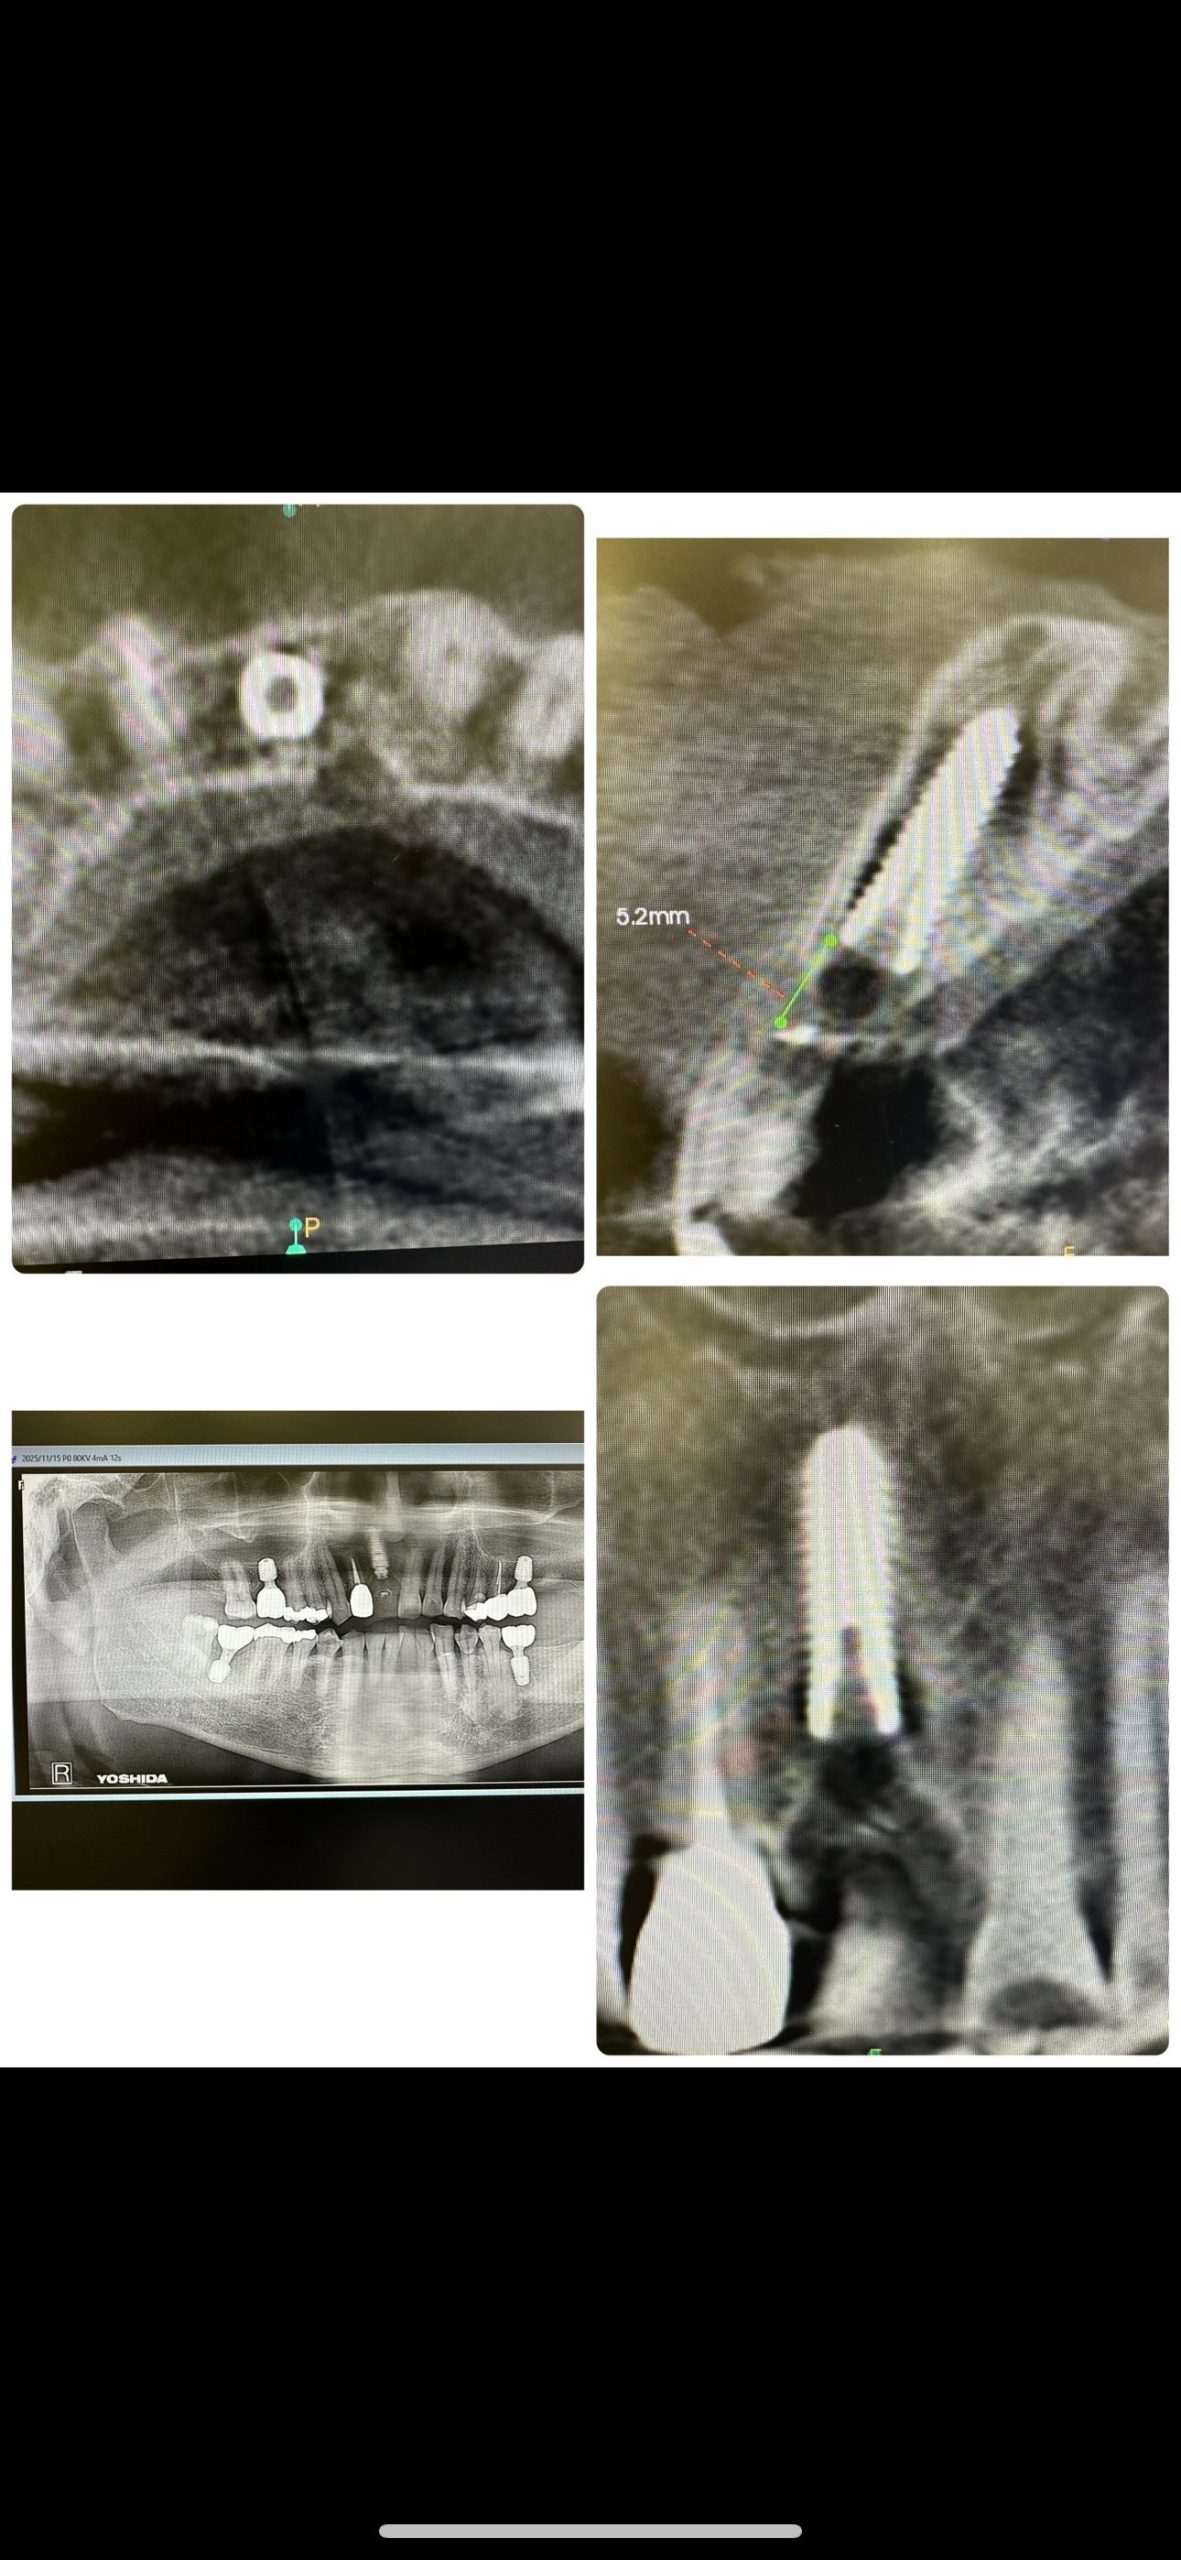

歯性上顎洞炎、順調に回復傾向